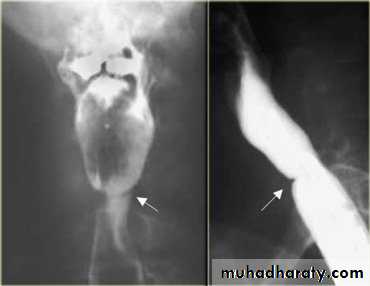

Sliding herniaOn the left initially, GE junction is below the esophageal hiatus. Later, stomach protrudes through hiatus

Para esophageal hernia

On the far left gas filled gastric funds (asterisk) protrudes through hiatus but GE junction (arrow) is below diaphragm• Thin mucosal fold (membrane)